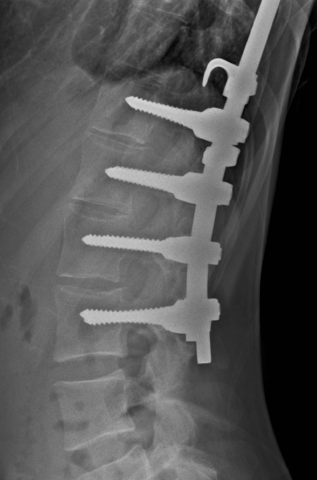

Seems like her epidural space should be intact after this Harrington Rod type procedure she had as a teenager, correct? There really is no decompression/lami type element to the procedure it appears...

Would you put a needle in there for SCS or ESI?

Thread catheter at lower interspace or caudal catheter and run some contrast to confirm?

Epidurogram with catheter to assess feasibility, but I'm still not sure what the pain pattern here is.

With the harrington rods, I think the issue is more the lamina hooks or wires causing scarring, making it hard to drive, and taking up space, but her setup doesn't look like it has any significant hooks above T11.